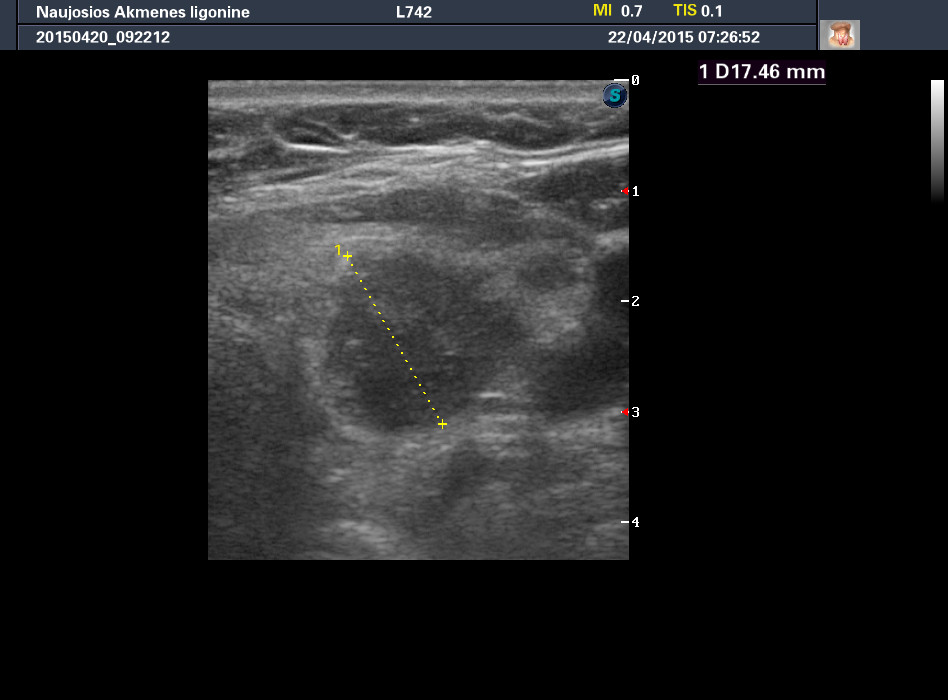

Случай 1

Женщина 67 лет, жалоб нет. Рост узла за год +3 мм. Регионарные ЛУ не увеличены.

apr222015072652_0.jpg